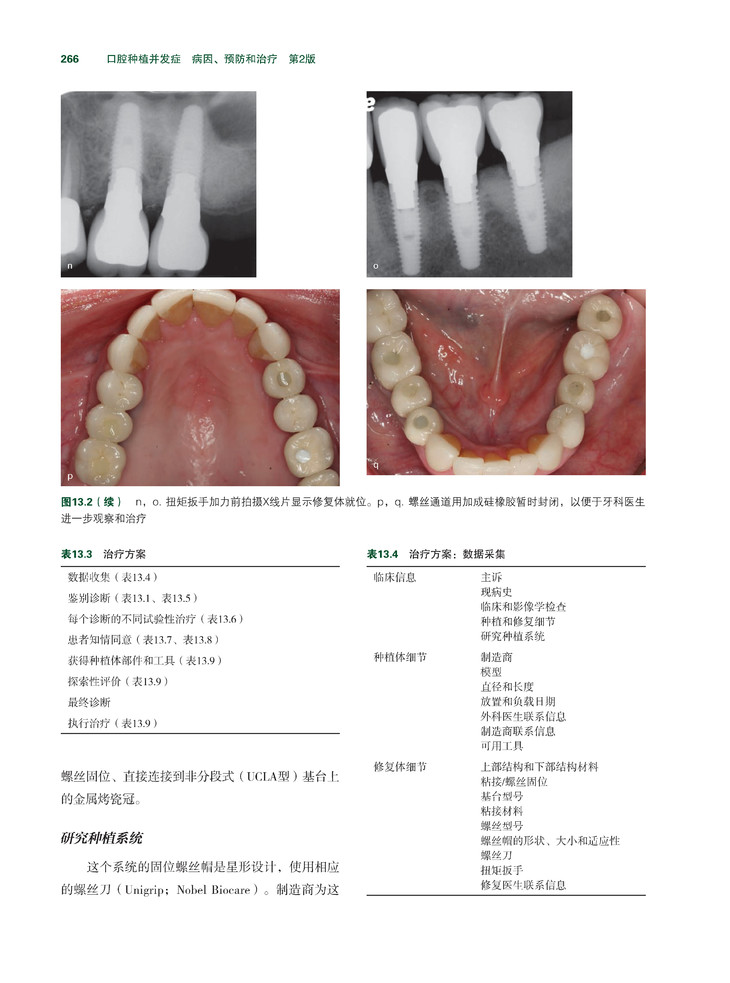

牙种植已成为最常用和发展最快的代替缺失牙的修复技术。虽然种植牙以可预期性、良好的功能和耐用性赢得患者和医生的青睐,但其并发症可能发生在从患者评估到维护治疗的任何阶段。

《牙种植并发症:病因、预防和治疗》是第一本基于循证研究、为各个层次的临床医生提供全面临床知识的参考书。本书选取了口腔临床与种植牙相关的各专业各具特点的典型病例,既包含了最常见的种植牙并发症,也包含了罕见但独特的种植牙并发症。 本书在内容的编排上结构清晰,包括牙种植的诊断,牙种植的治疗计划,以及种植体放置、修复、和维护治疗,牙种植等各个时期的并发症等。此外,与骨增量和上颌窦提升相关的并发症也给予了详细的讨论,尤其是其病因和预防。本书的每一章都力求做到了言简意明、层次清晰,每章最后都有“重点提示”总结该章的基本要点。除临床知识外,本书还为读者提供了种植牙领域的最新工业标准,并探讨了与种植牙相关的医学法律问题。书的最后以一组由该领域的专家提供的典型病例作总结,展示了与种植牙相关的复杂并发症及其多方面的治疗措施。